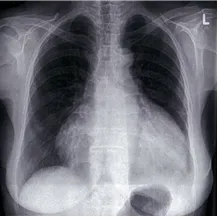

72세 남성이 1주일 전부터 호흡곤란을 호소하며 내원하였다. 폐암으로 항암화학요법 시행 중이며, 혈압은 82/50mmHg, 맥박은 115회/분, 호흡수는 22회/분, 체온은 36.7℃로 측정되었다. 심장 청진 시 심장박동이 미약하게 들렸다. 환자의 가슴 X선 사진을 참고하여 다음 중 가장 적절한 검사를 선택하시오.

Water bottle appearance

Imp: 심장눌림증(cardiac tamponade)

• 다량의 pericardial effusion으로 저혈압, 심음 감소, 호흡곤란이 동반될 수 있으며 CXR 상 관찰되는 water bottle appearance도 이에 합당한 소견이다.